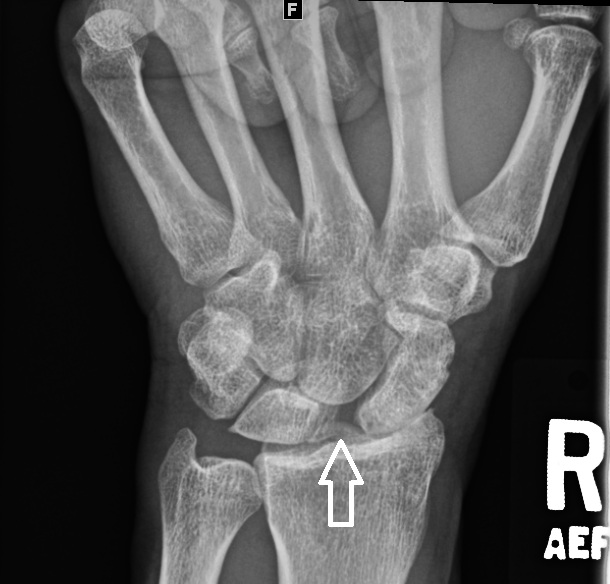

using the AP view of the wrist, identify distance between scaphoid and lunate. The distance is between the proximal ulnar corner of the scaphoid and the proximal radial corner of the lunate.

if > 4 mm then Terry-Thomas sign; widened ( RID5797 ) carpal joint space

how to draw the scapholunate distance